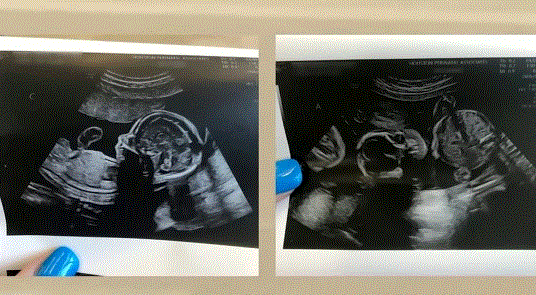

Belə ki, 2021-ci ildə Qabi Xaqler və ailə psixoterapevti olan 50 yaşlı əri Patrik son olaraq 4-cü övlad dünyaya gətirmək qərarına gəliblər. Cütlüyün bir ortaq Semmi adlı oğlu, digər nikahlardan da hərəsinin bir uşağı olub. Bir müddətdən sonra hamilə olduğunu öyrənən Qabi planlı müayinəyə gedib. Bu zaman məlum olub ki, qadın bir yox, 4 uşaq gözləyir. Nəticədə onu 4 oğlu olub.